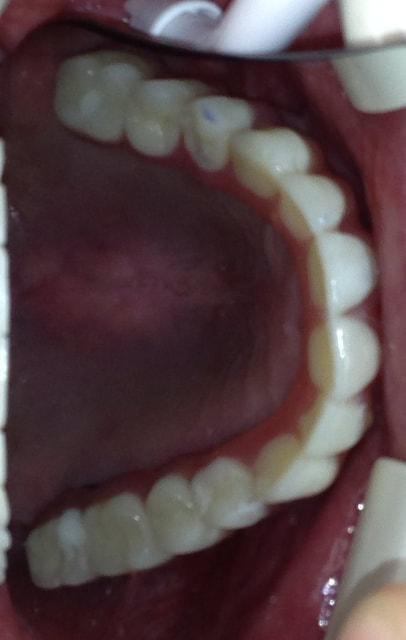

ALL-ON-6 BRIDGE

This patient presented with the poor prognosis for his upper teeth, severe bone loss and bite problems.

After thorough evaluation Dr. Andrews recommended ALL-ON-6 fixed implant bridge. The entire surgical stage, including extractions of all remaining upper teeth, bi-lateral sinus lift (right and left side), multiple bone grafts and placement of all 6 dental implants was accomplished by Dr. Andrews in one visit. Six months later the full upper arch dental implant bridge was delivered.